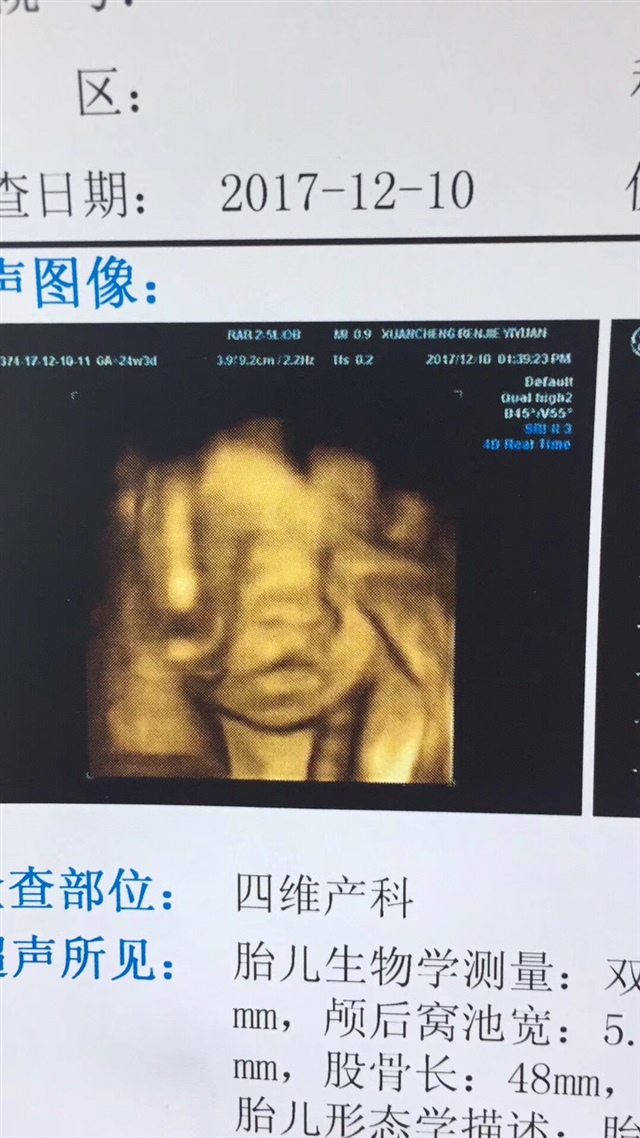

几周测四维可以拍到这个?好可爱,感觉像在揉眼睛^_^